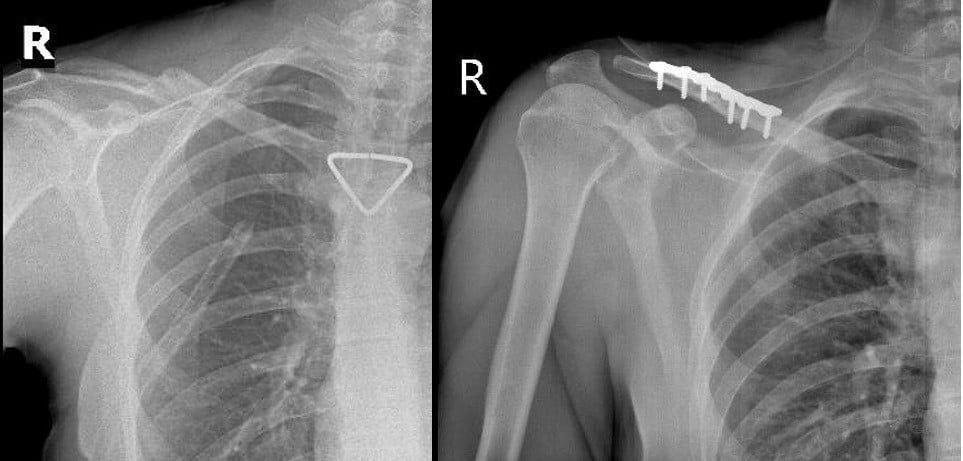

Tại đây, sau khi hội chẩn cùng bác sĩ gây mê hồi sức, người bệnh được đánh giá đủ điều kiện an toàn để thực hiện cuộc phẫu thuật thứ hai: kết hợp xương đòn phải bằng nẹp vít. Ca mổ được thực hiện bởi ê-kíp: BS.CKII Trần Văn Dương, BS Phạm Ngọc Huy.

Phẫu thuật diễn ra thuận lợi, nẹp vít được đặt vững chắc, trục xương phục hồi giải phẫu tốt. Sau mổ, người bệnh hồi phục nhanh, vận động tay phải cải thiện từng ngày và xuất viện sau 4 ngày điều trị tại khoa trong tình trạng sức khỏe ổn định.

Hình 2. Hình ảnh Xquang trước và sau mổ. Nẹp vít được đặt vững chắc, trục xương phục hồi giải phẫu tốt